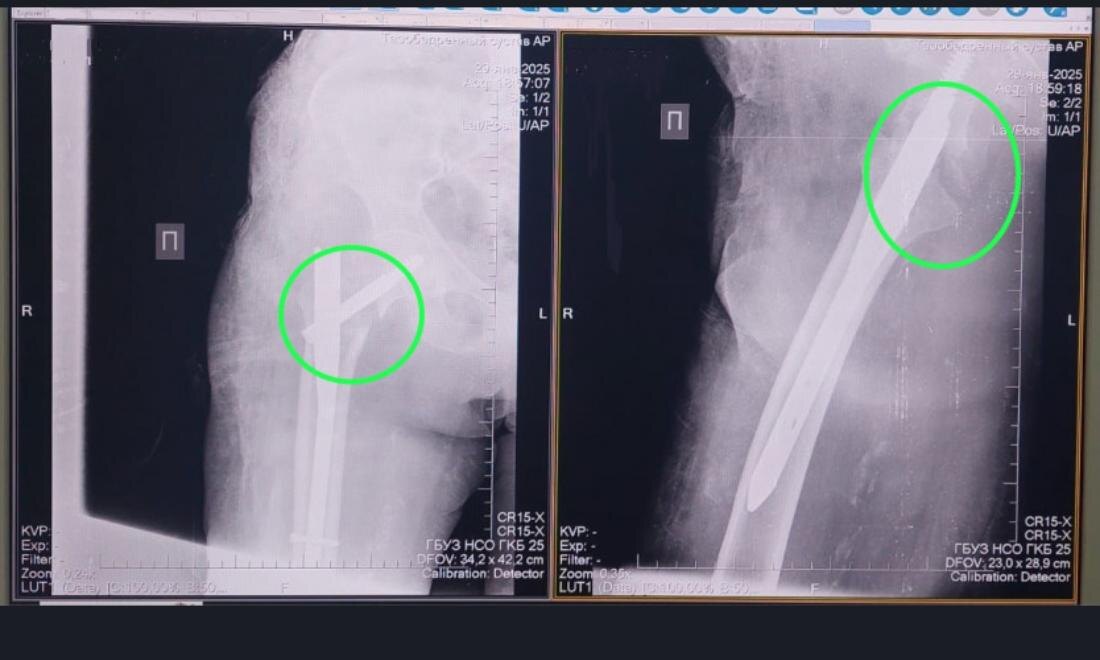

91-летняя жительница Болотнинского района получила перелом проксимального отдела бедренной кости. Пожилая женщина споткнулась дома о порог и упала.

«В ГКБ № 25 нашей пациентке провели остеосинтез – сопоставили костные отломки и зафиксировали их металлической конструкцией. Сейчас она уже дома, перед выпиской родственники приобрели ходунки. Она уже получает дозированную лёгкую нагрузку на сустав. В таких операциях даже в 90 лет почему не отказывают? Потому что чем быстрее пациента активизировать, на ноги поставить, тем прогноз благоприятнее», – подчеркнул Абдель Таймусаев.